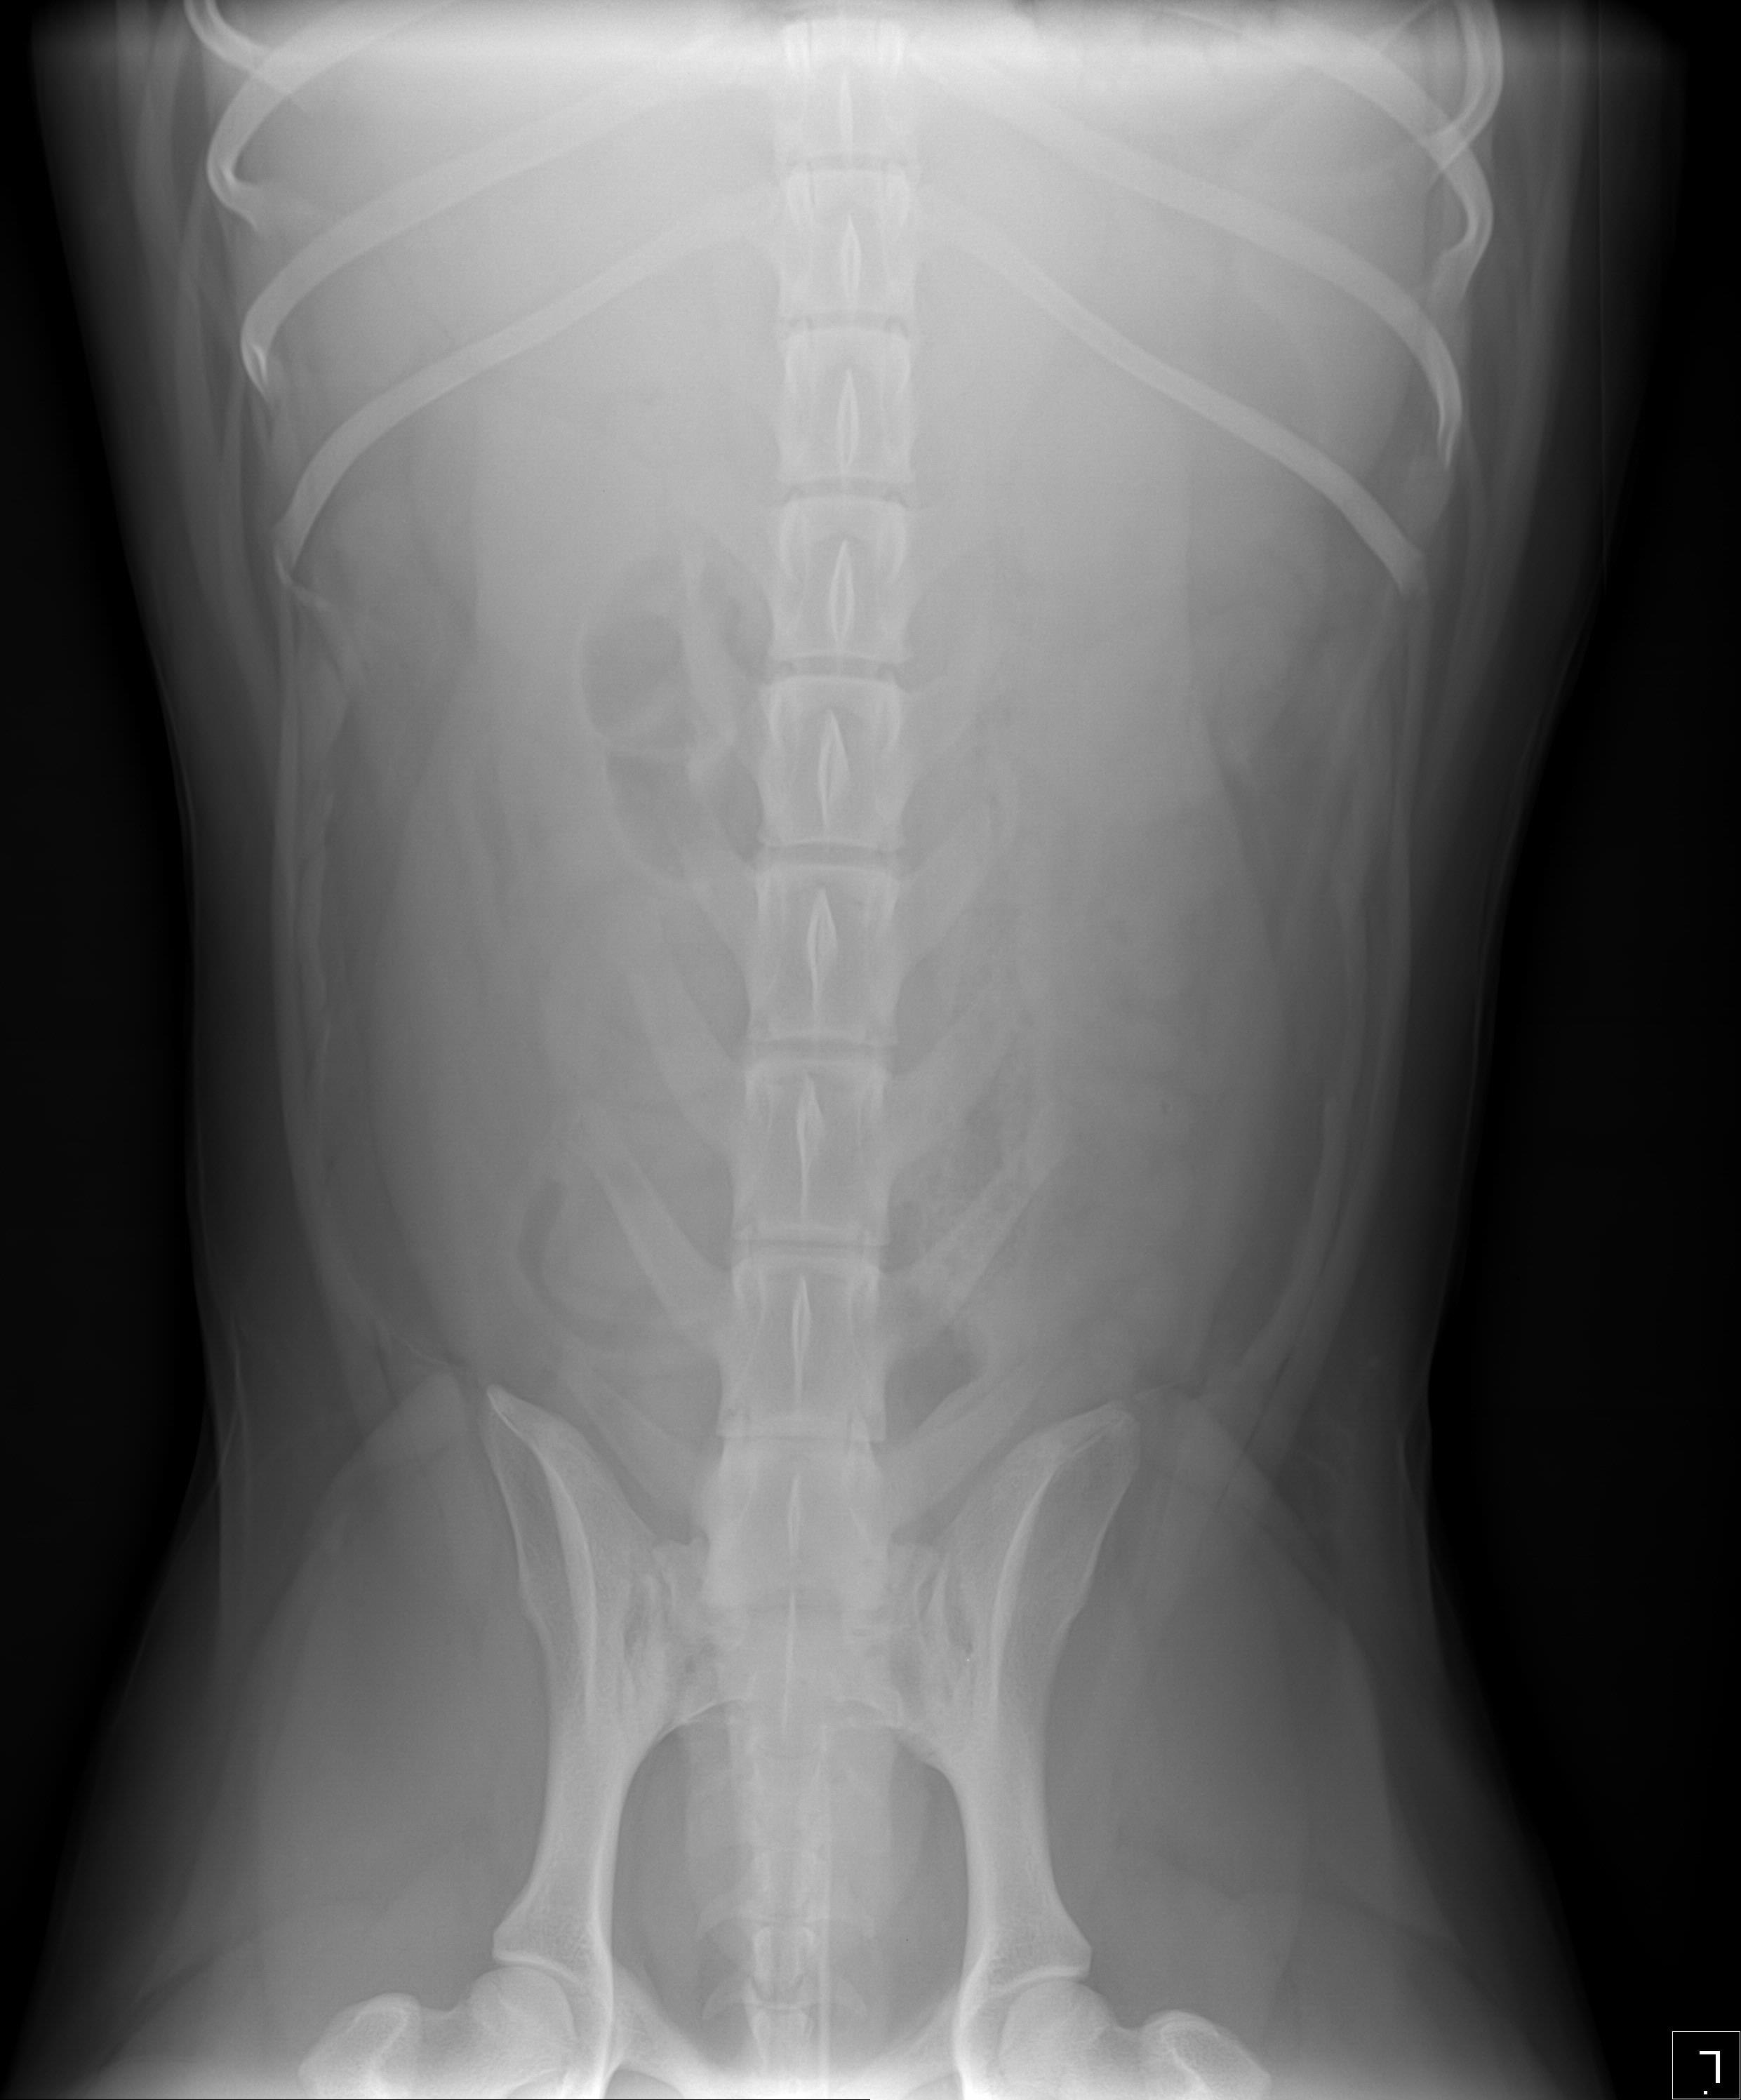

Friday Kyro swallowed big bone off street. Sat & Sun lot of Diarrhea & some vomiting. Sun an Emergency Vet took X ray. Emergency Vet saw piece in stomach. Prescribed Metronidazole & Famotidine, suggested 1/4 cup of rice & 1/4 cup of chicken as feedings which I did a few. Today my Vet said NO rice but feed chicken, pumpkin and peas. My Vet did NOT see bone in stomach. Sunday only slight water as bowl movements. Today no bowl movements. Kyro eating & acting normal. No extended stomach or delicate